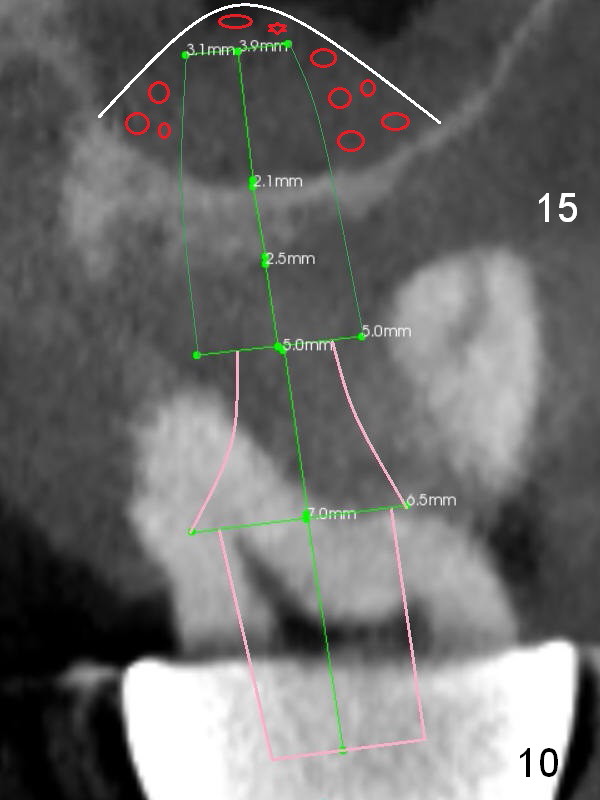

Alginate impression will most likely dislodge #11-15 loose FPD. Start osteotomy at #11 and 15 first (Fig.6, 10) and use the teeth #9 and 10 as trajectory reference. Prepare PRF (Fig.10 white curved line) and Magic Lifter for #15.

In case primary stability is questionable for example at #15 (Fig.10), consider placing implants at #12 and/or 14 (Fig.7,9).